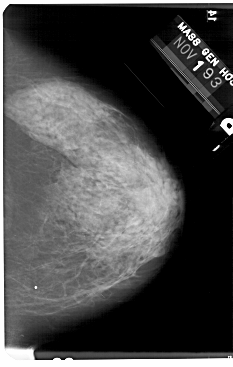

A_1732_1.RIGHT_CC

RIGHT_MLO LINES 5491 PIXELS_PER_LINE 3526 BITS_PER_PIXEL 12 RESOLUTION 43.5 NON_OVERLAY